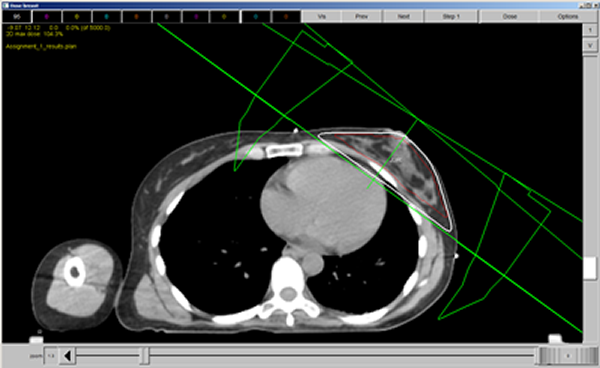

Another way to evaluate the plan is too look at the overall dose coverage. To do this, we will be looking at the 95% line and evaluating whether or not it is at an acceptable level.

First we will do this in the dose window. For this example below, I have turned off all dose likes except for the 95% line (in white). I have also turned on the target volume PTV (in red)

This image illustrates complete coverage of the PTV by the 95% dose line on this cut. When in the treatment planning system, we will scroll through the plan and check the coverage of all of the cuts.